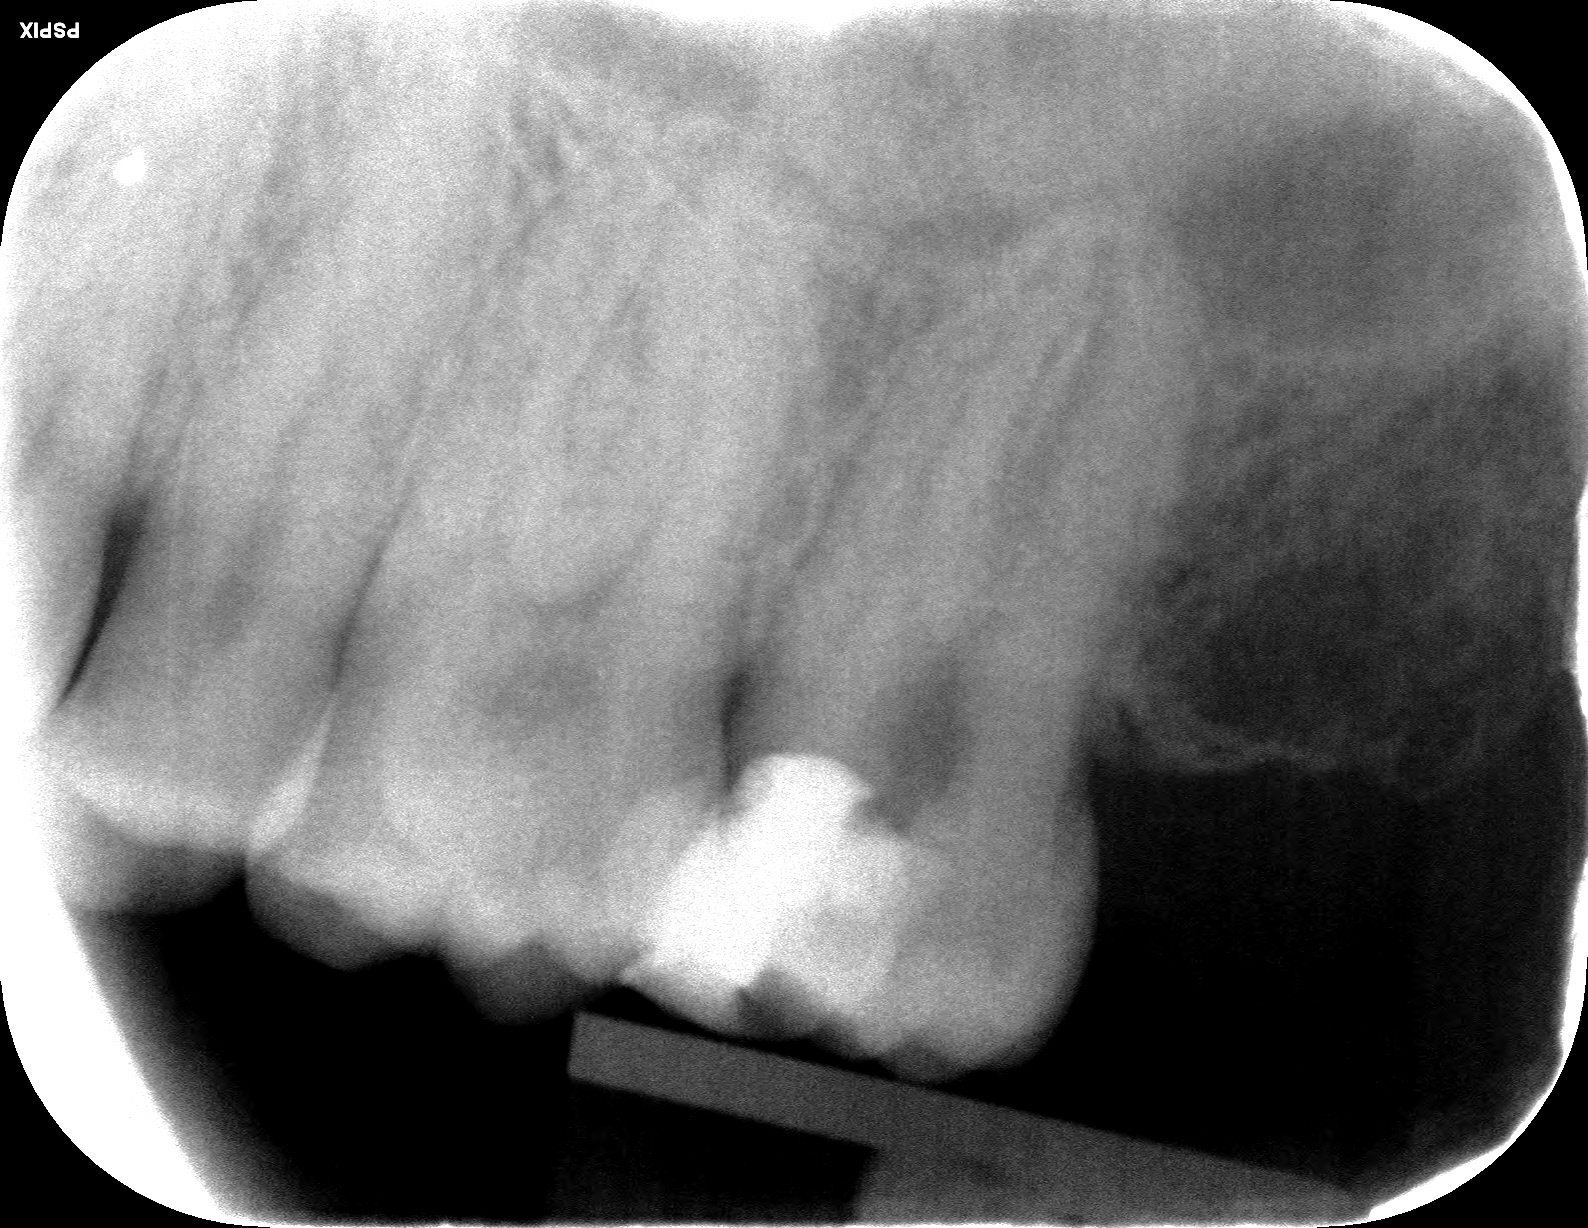

Ik heb een foto van na de endo start erbij gevoegd in deze bericht, mits dat het helpt.